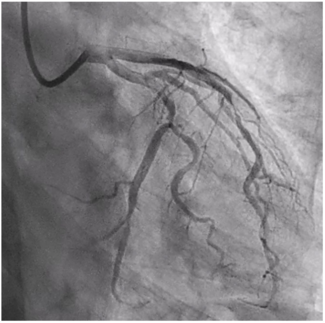

A 63-year-old male with a history significant for 50 pack years of tobacco use and a cerebrovascular accident presented with unstable angina. His electrocardiogram (ECG) showed sinus bradycardia with nonspecific ST/T wave changes. Coronary...